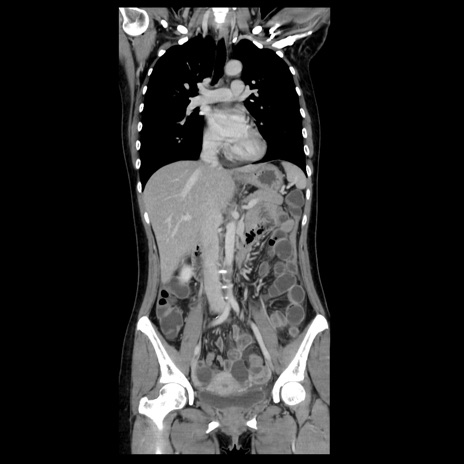

症例39(冠状断像)

【症例】40歳代女性

【主訴】上下腹部痛

【現病歴】2日目から下腹部痛あり。夜間は痛みで眠れなかった。昨日より上腹部痛と下痢が出現。臥位で痛みは軽快したため、休んでいた。本日になって臥位でも立位でも痛みが強くなってきたため救急要請。

【既往歴】子宮内膜症

【身体所見】部:平坦・軟、左上下腹部に圧痛あり、反跳痛あり。

【データ】WBC 21800、CRP 26.78

CT